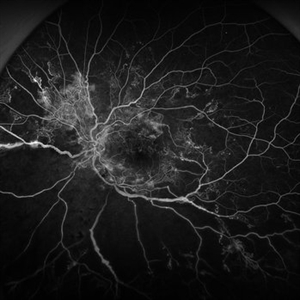

Severe Proliferative Diabetic Retinopathy

Jan 10 2024 by Ahmad B. Tarabishy, MD

33 year old female with 1 month history of vision loss right eye. Severe PDR was noted with VH and a TRD with severe FVP present OD.

Photographer: Sharon Story, Lakeland Eye Clinic

Imaging device: Optos

Condition/keywords: diabetic blindness, fibrovascular proliferation, nonperfusion diabetic retinopathy, peripheral retinal nonperfusion, proliferative diabetic retinopathy (PDR), tractional retinal detachment